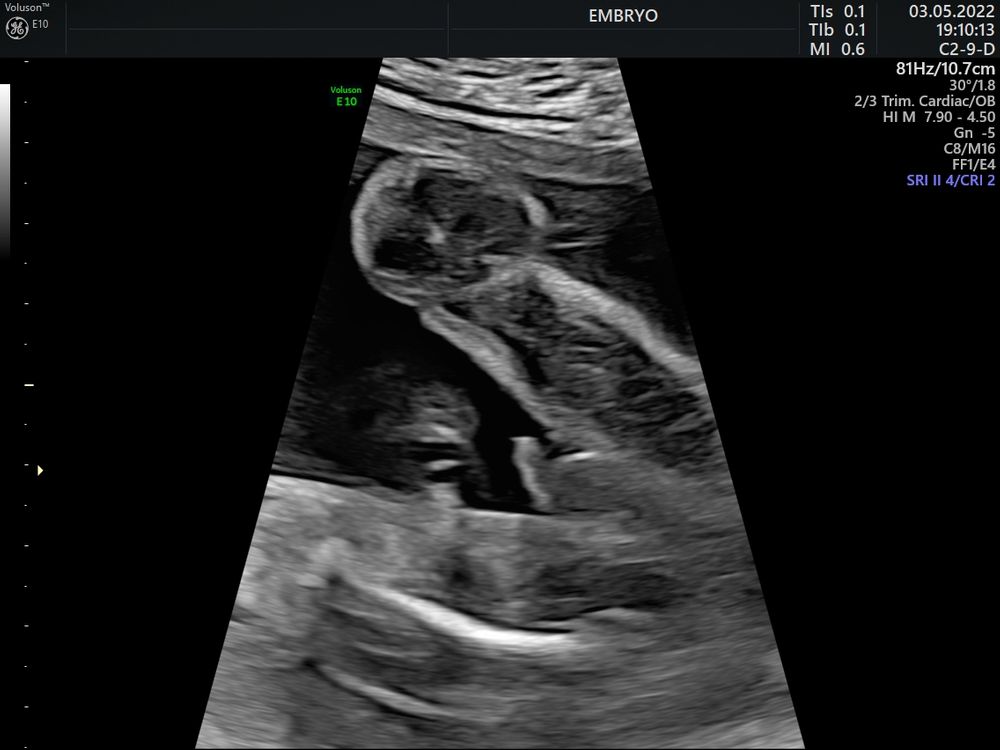

Пол малышаВсем привет, какова вероятность ошибки с полом на узи в 29 недель?

В 15, 17 и 21 - мальчик 100%

Яна, Вот и у меня все эти узи было очевидно что мальчик( фото прилагаю) , а сегодня ошарашили, думаю врач плохо посмотрела и все таки у нас пацан